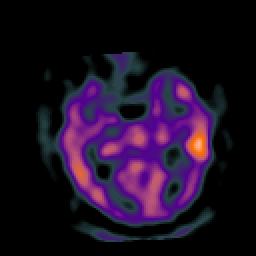

Subacute Stroke, overlay -- Slice #10

[Home][Help][Clinical] Slice 10